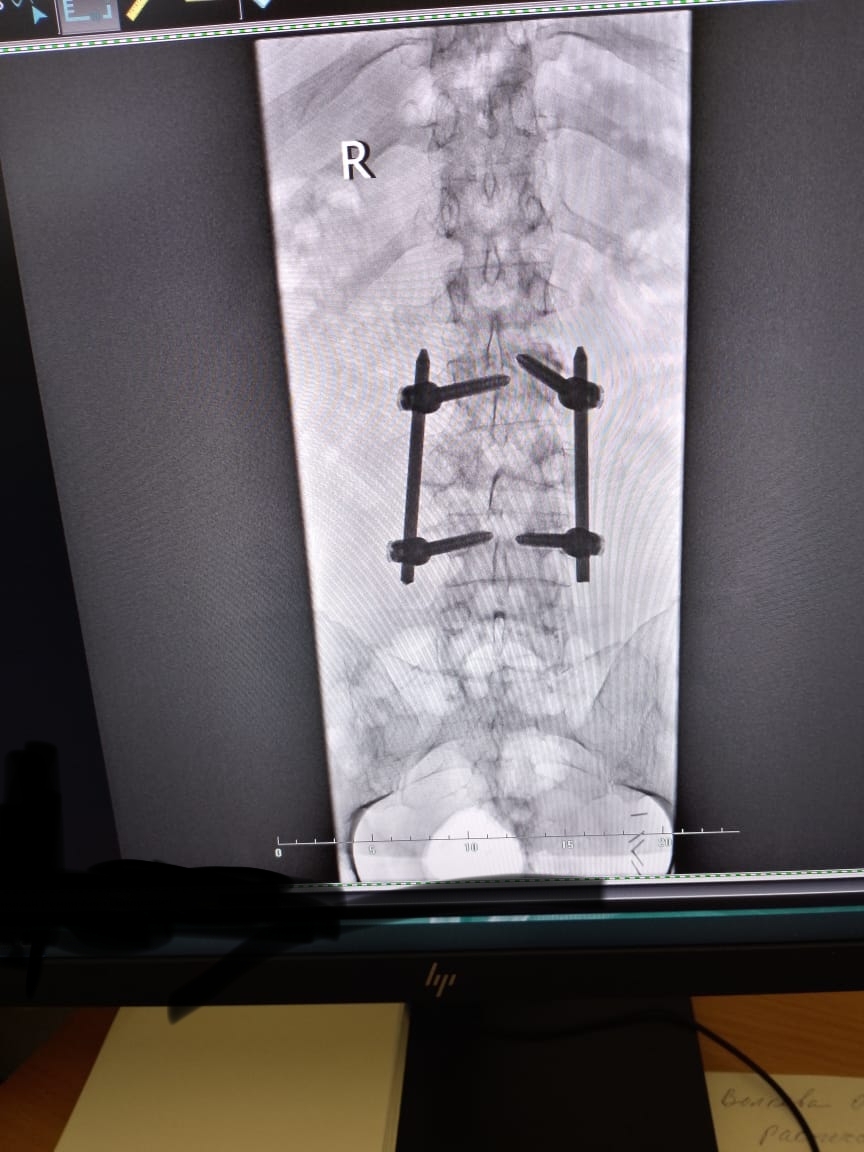

По позвоночнику, так как один болт решил сместится то ортопед ( лечащий)советует переделать конструкцию ( расширить на другие позвонки , чтобы распределить нагрузку как я понял) или поставить типо протеза" диск " . Операция на переделку по квоте - очереди 3 месяца+, на протез " диск" - пол года +. Или на платной основе, переделка 200+-, протез 400+-. Но другой ортопед , из онко больницы в Москве, советовал не лезть туда - потому что сломанный позвонок закостенел уже , но если болты " двигаться " будут то будет больно. Теперь я в раздумьях, с одной лучше сделать и не будет ограничений физических- но опять восстанавливаться долго. А с другой стороны опять операция , не будет ли по онкологии осложнений потом. Вы как думаете? Сейчас из за позвоночника ограничения - тяжёлое не поднимать, и сидеть долго не могу. Часто с палкой хожу, но это еще из за ноги...